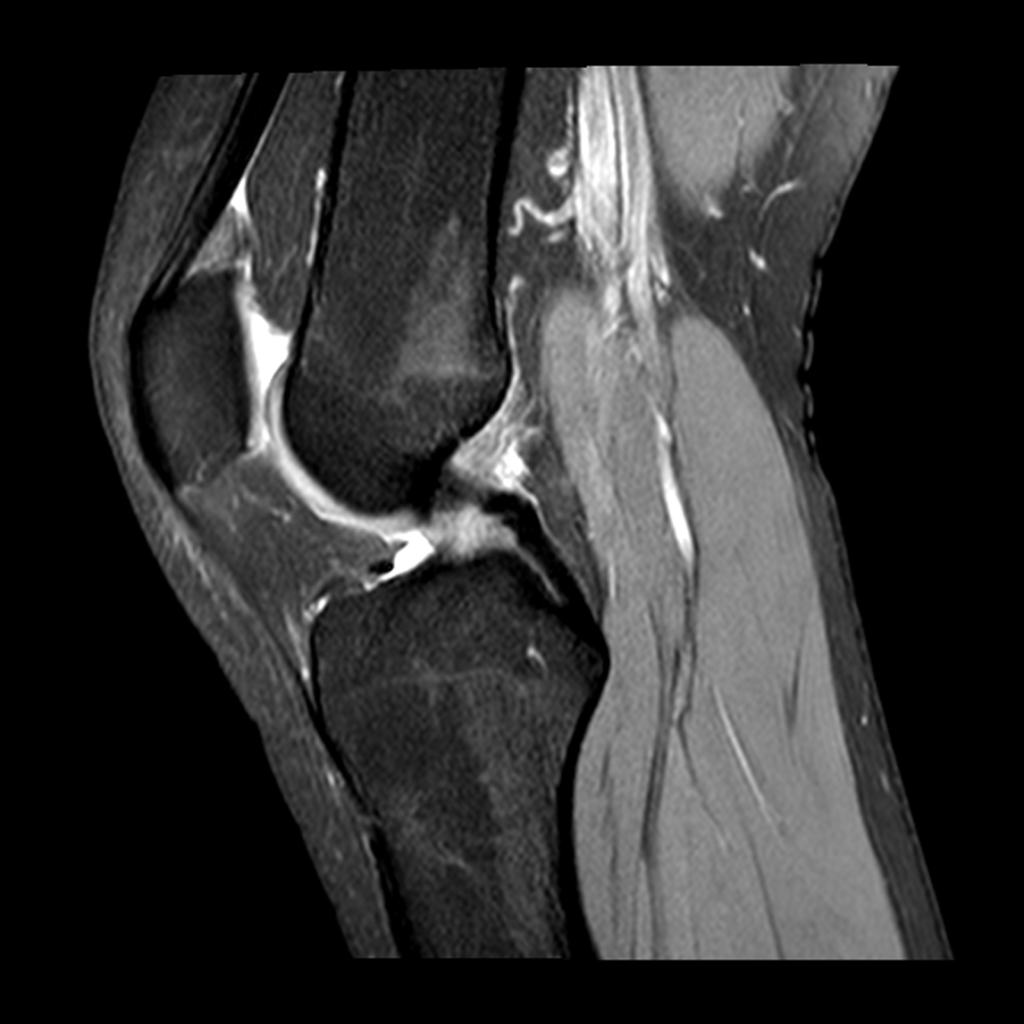

MRI

- MRI stands for magnetic resonance imaging

- MRI does not use ionizing radiation and so will not cause cancer

- The process of obtaining an MRI is significantly slower than getting a CT scan